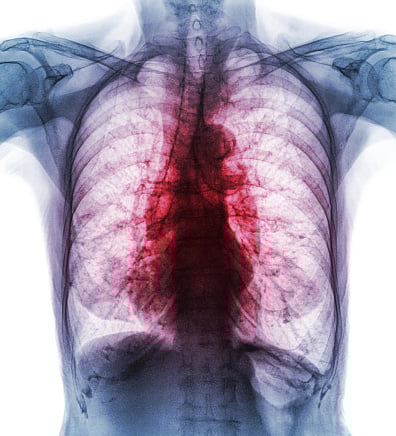

“If endobronchial combustion occurs, patients may suffer critical internal burns to the airway or lungs that may result in a requirement for additional medical intervention, prolonged procedure, extended hospitalization or ICU care, and death,” the company said.

Such a combustion can also damage or break device components that may injure or remain unintentionally in the patient and require retrieval or surgical removal, it added.